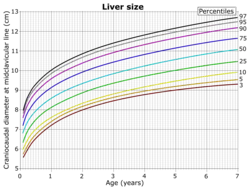

On abdominal ultrasonography, the liver can be measured by the maximum dimension on a sagittal plane view through the midclavicular line, which is normally up to 18 cm in adults.[2] It is also possible to measure the cranio-caudal dimension, which is normally up to 15 cm in adults.[2] This can be measured together with the ventro-dorsal dimension (or depth), which is normally up to 13 cm.[2] Also, the caudate lobe is enlarged in many diseases. In the axial plane, the caudate lobe should normally have a cross-section of less than 0.55 of the rest of the liver.[2]

Other ultrasound studies have suggested hepatomegaly as being defined as a longitudinal axis > 15.5 cm at the hepatic midline, or > 16.0 cm at the midclavicular line.[17][18]